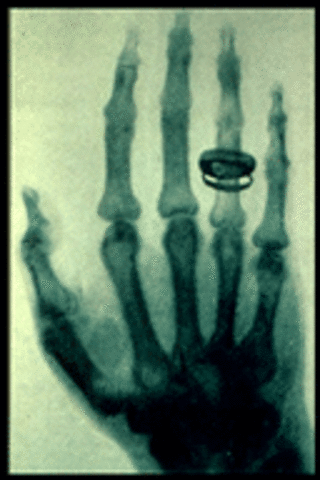

• X-Rays were discovered

X-Rays were discovered

William Roentgen found that X-Rays would pass through human tissue leaving the bones and metals visible.